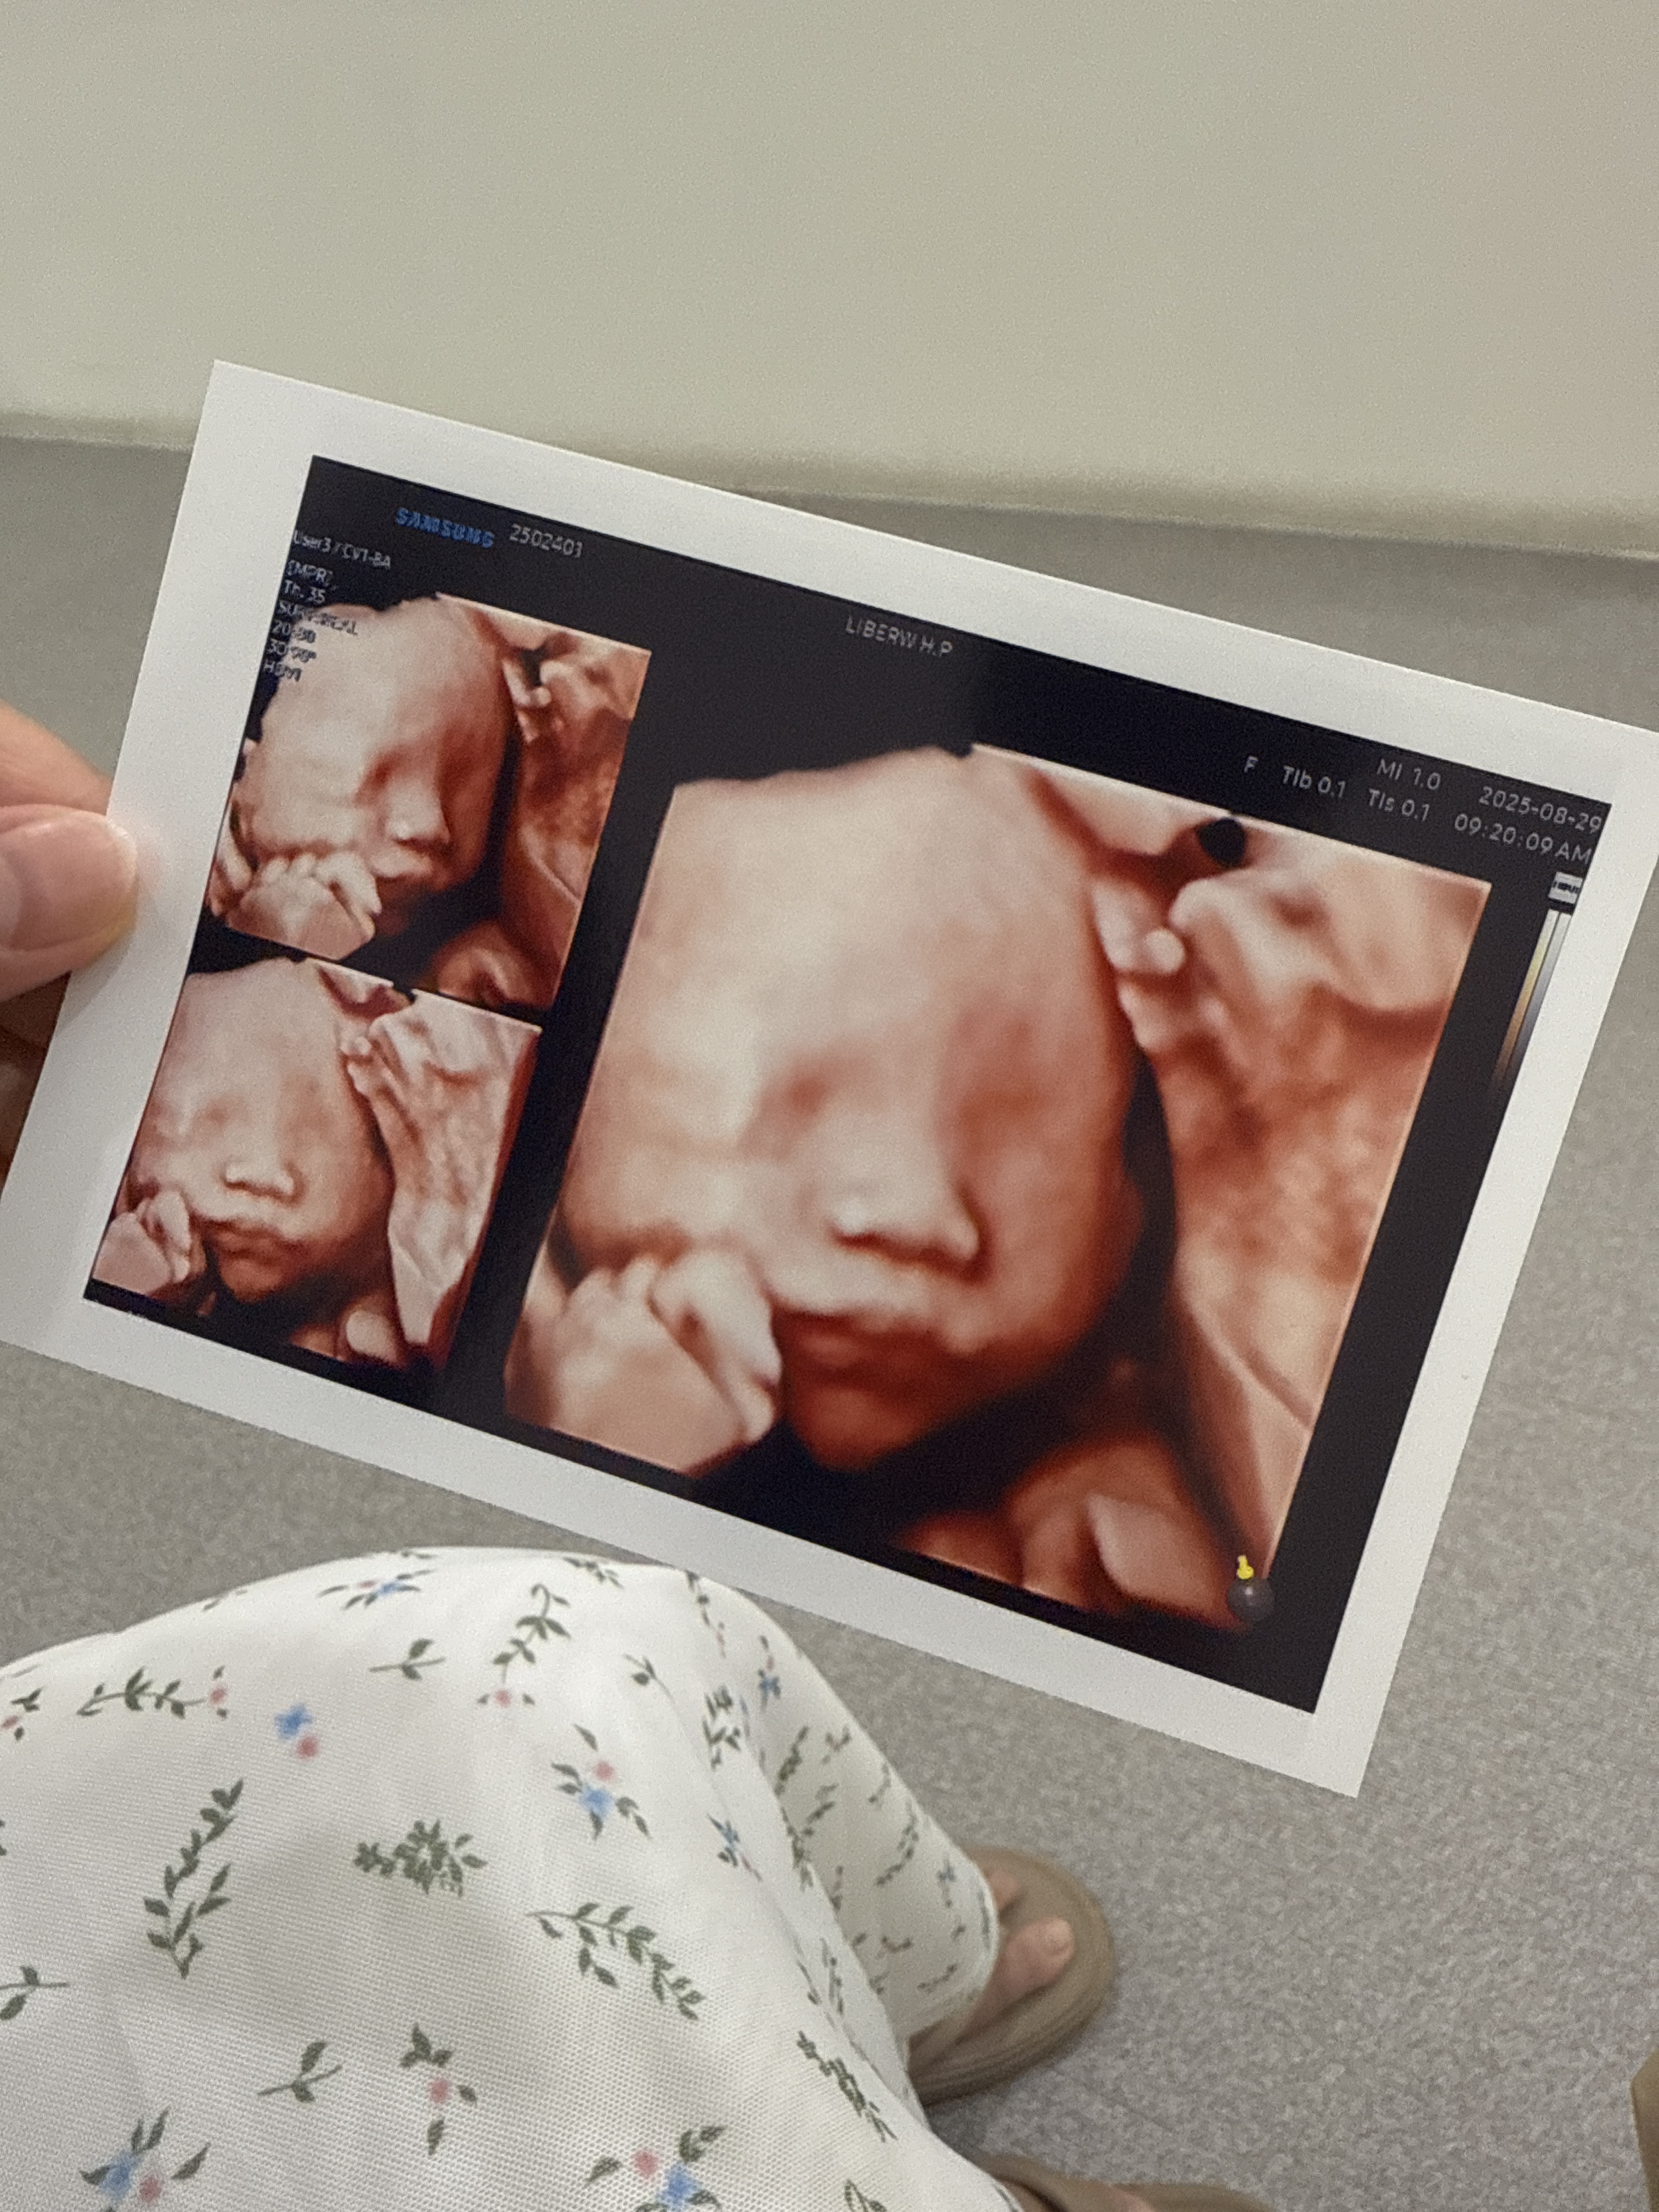

드디어 성공한 입체초음파

3차까지 실패하면 못본다해서 걱정했는데

성공했다 얏호👏👏

진짜 조~금 기대했는데,

사진 받으니까 너무 귀여워서 혼났다ㅠㅠ

손으로 턱 괴고 있었는데,

왤케 귀여운거니 사탕아...

내 최애사진은 입 벌린 사탕이ㅋㅋㅋㅋ

양수 마시는건지 입벌리고 있던게

딱 포착됬다 !!!

귀여워 죽겠네🤍🤍🤍

같이 찍어주신 사탕이 손이랑 발

길쭉길쭉한게 이뻤다..^^